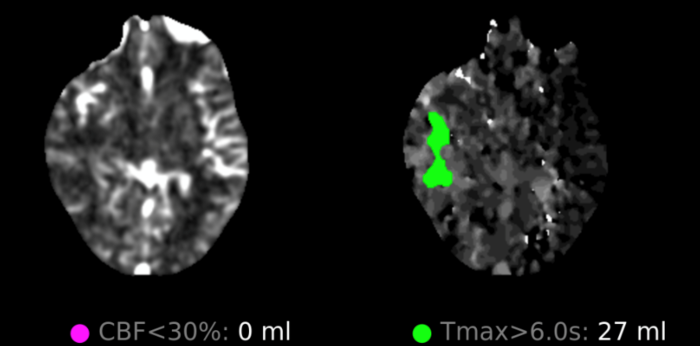

Initial objective data included T 37C, HR 85, RR 20, BP 153/109, spO2 98%. Glucose 102. Basic labs obtained and were unremarkable. Patient was rapidly taken to CT for stroke imaging. No contraindications to thrombolytics were identified. At 1708, noncontrast head CT showed no hemorrhage, but an abnormal hypodensity along the right middle cerebral artery concerning for an air embolus was visualized. CT angiogram head and neck was also suggestive of air embolus and CT perfusion brain demonstrated 27 mL of critical hypoperfusion at the right posterior middle cerebral artery distribution.

Figure 4: CT perfusion brain showing calculated 27 ml area of critical hypoperfusion with >6 seconds time-to-maximum filling.